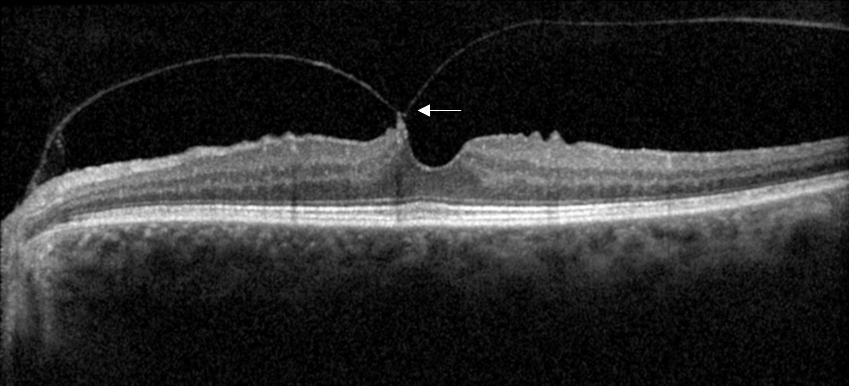

OCT en coupe avec attache vitréo maculaire

OCT en coupe avec attache vitréo maculaire (flèches)